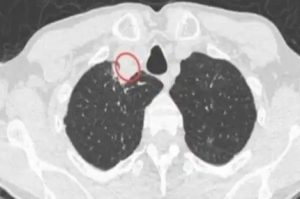

• सीटी स्कैन किए जाने पर उनकी गर्दन में एक पैराट्राचेयल फोड़ा नजर आया. जांच के बाद डॉक्टर्स ने इस फोड़े को हटा दिया और टेस्ट के लिए एक सैंपल, विश्व स्वास्थ्य संगठन के रेफरेंस एंड रिसर्च ऑन फंगी ऑफ मेडिकल इंपॉर्टेंस के सहयोग केंद्र पर भेजा. संक्रमित शख्स को डायबिटीज, एचआईवी संक्रमण, गुर्दे की बीमारी या फिर किसी और तरह की पुरानी बीमारी नहीं रही थी.